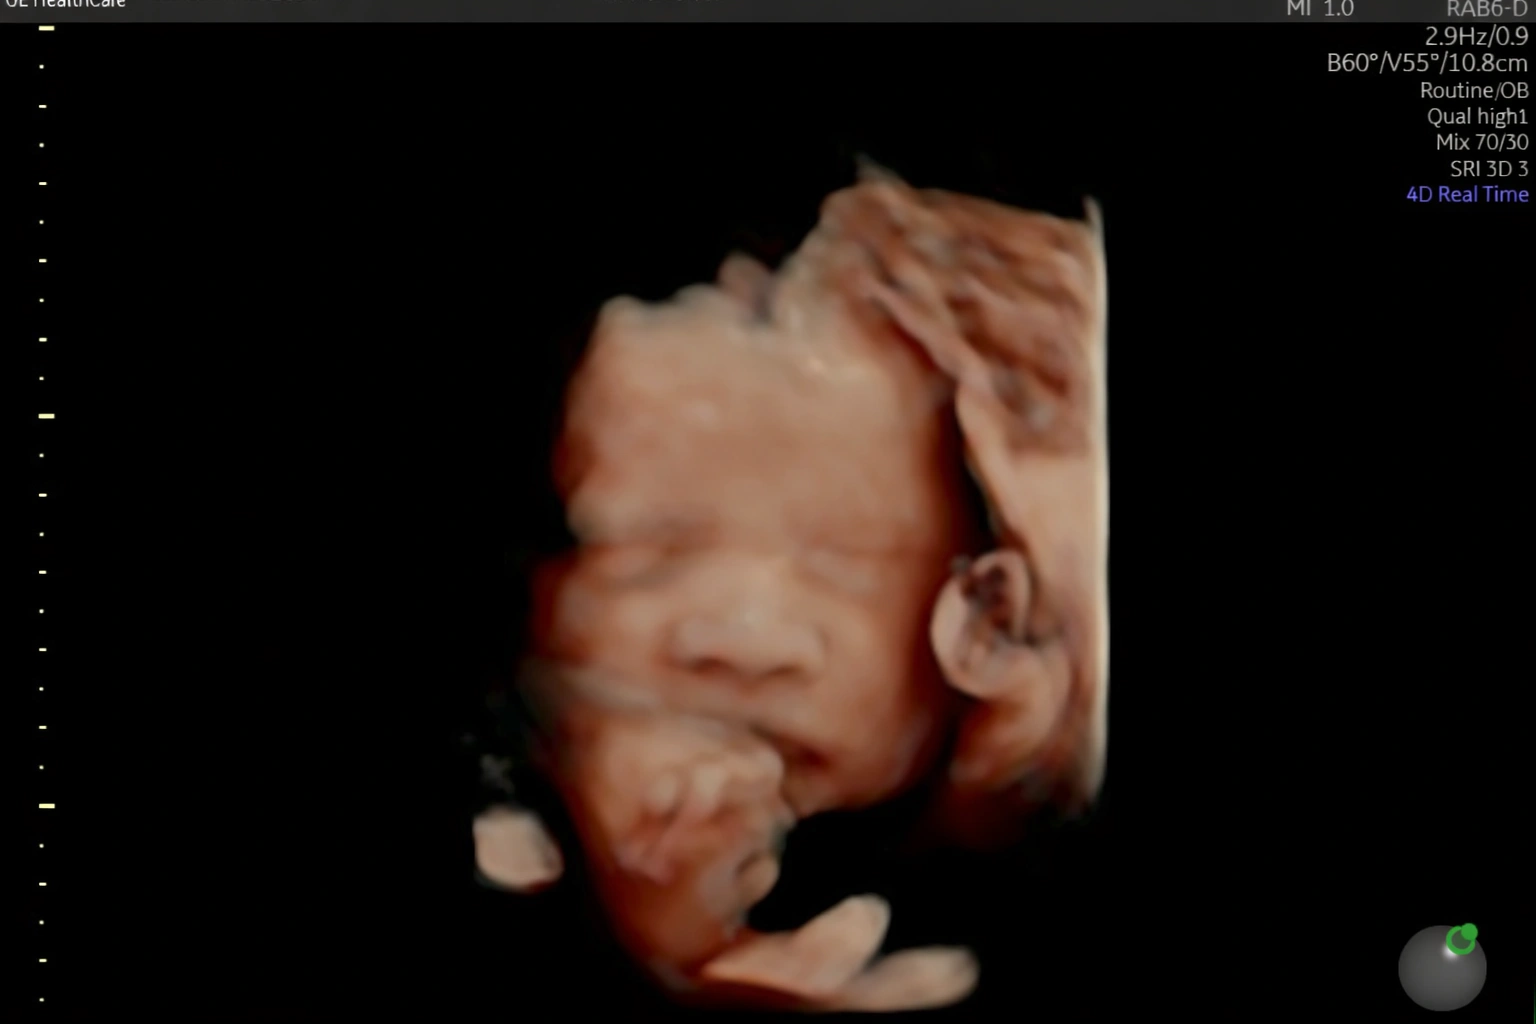

Acompanho detalhadamente toda a evolução do seu bebê ainda na sua barriga.

Realizo diversos tipos de ultrassonografia para garantir que seu bebê chegue ao mundo com saúde.

Estou pronta para realizar diagnósticos precisos sobre como anda a saúde do seu bebê ainda ai dentro da sua barriga. Realizo toda e qualquer tipo de ultrassonografia obstetríca.